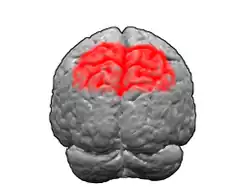

Image of brain with Brodmann area 7 shown in red | |

Brodmann area 7 is one of Brodmann's cytologically defined regions of the brain corresponding to precuneus and superior parietal lobule (SPL). It is involved in locating objects in space. It serves as a point of convergence between vision and proprioception to determine where objects are in relation to parts of the body.[1]

In humans

Brodmann area 7 is part of the parietal cortex in the human brain. Situated posterior to the primary somatosensory cortex (Brodmann areas 3, 1 and 2), and superior to the occipital lobe, this region is believed to play a role in visuo-motor coordination (e.g., in reaching to grasp an object). In addition, area 7 along with area 5 has been linked to a wide variety of high-level processing tasks, including activation in association with language use.[2] This function in language has been theorized to stem from how these two regions play a vital role in generating conscious constructs of objects in the world.[3]

Brodmann area 7 spans both the medial and lateral walls of the parietal cortex. The medial part of Brodmann area 7 is called precuneus. Laterally, it is called the superior parietal lobule (SPL). At the base of the SPL is the intraparietal sulcus, below which is the inferior parietal lobule (IPL), which in turn divides into Brodmann areas 39 (angular gyrus) and 40 (supramarginal gyrus).